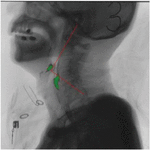

Recognizing the direction of an X-ray photograph is a challenging subject. Normally, the swallowing posture and position of the patient vary, and the position of the body’s oral cavity and the length of the pipe will also vary at different ages, as shown in the following figure. As a result, the acquired video frame sequence is largely related to the radiologist’s shooting situation.

Through observation, we can find that the position of the cervical spine has a relatively high degree of recognition. We can calibrate the position of the cervical spine to track the movement trajectory of the fluid barium. As a model verification and correction link, it will help us to improve the recognition accuracy. Experimental results As shown in the figure below.

images

Figure 9 Taking the cervical spine as the coordinate system.

Figure 10 Taking the cervical spine as the coordinate system (enlarged display).